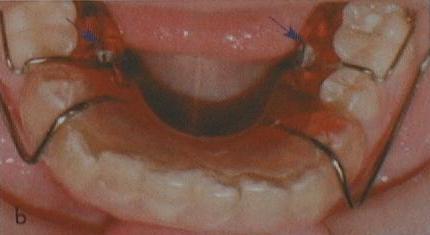

Das letzte Mundfoto zeigt schließlich einen Fall mit größerer „Schraub-Arbeit“ im Unterkiefer zeitgleich mit dessen Lage-Korrektur: die Lücken von nicht angelegten 5ern wurden mit Zugschrauben (kleine blaue Pfeile) „zugeschraubt“, d.h. die 6er wurden an Schraubsegmenten nach vorn geführt (mesialisiert). In begrenzterem Maße würde auch ein „Zurückschrauben“ (Distalisieren) funktionieren, wenn z.B. 6er aufgewandert sind oder Platzmangel besteht, der durch „Querdehnen“ nicht behebbar ist. In jüngster Zeit ist oft verkannt worden, dass Zähne bei Kindern eine Tendenz zum Senkrechtstehen haben, die weitgehend kippungsfreie Mesialisierungen oder Distalisierungen mit herausnehmbaren Zahnspangen ermöglicht. Immer vorausgesetzt, sie werden nicht „mehr geschraubt als getragen“ . Ein 5er-Lückenschluss wie oben ist selbst beim Erwachsenen mit Alignern beschrieben, ist also bei geeigneter Bauart auch dann noch mit Herausnehmbaren möglich.

In the last patient photo, large „screw work“ was accomplished simultaneously with bite shift. The permanent 5s were lacking, and the 6s were moved into their gaps by screwed segments (indicated by little blue arrows). Movements in opposite direction, as often required for space gain, also work by this method to some extent. It is often ignored that childrens´ teeth have a tendancy to stand upright, which allows „clean“ bodily shifts with well-designed removable braces – provided that they are sufficiently worn. Also for adults a closure of a 5-gap like above has been documented with removable aligners.

Le

dernier exemple montre un cas

d´une agénesie des 5s inférieures. Les 6s sont bien accrochies aux

segments de la plaque qui sont déplacés en avant avec des vérins

de traction (petites flèches bleues). En même temps que les 6s sont

déplacées dans les lacunes, une correction de la mandibule entière,

qui était nécessaire en plus, a été effectuée.